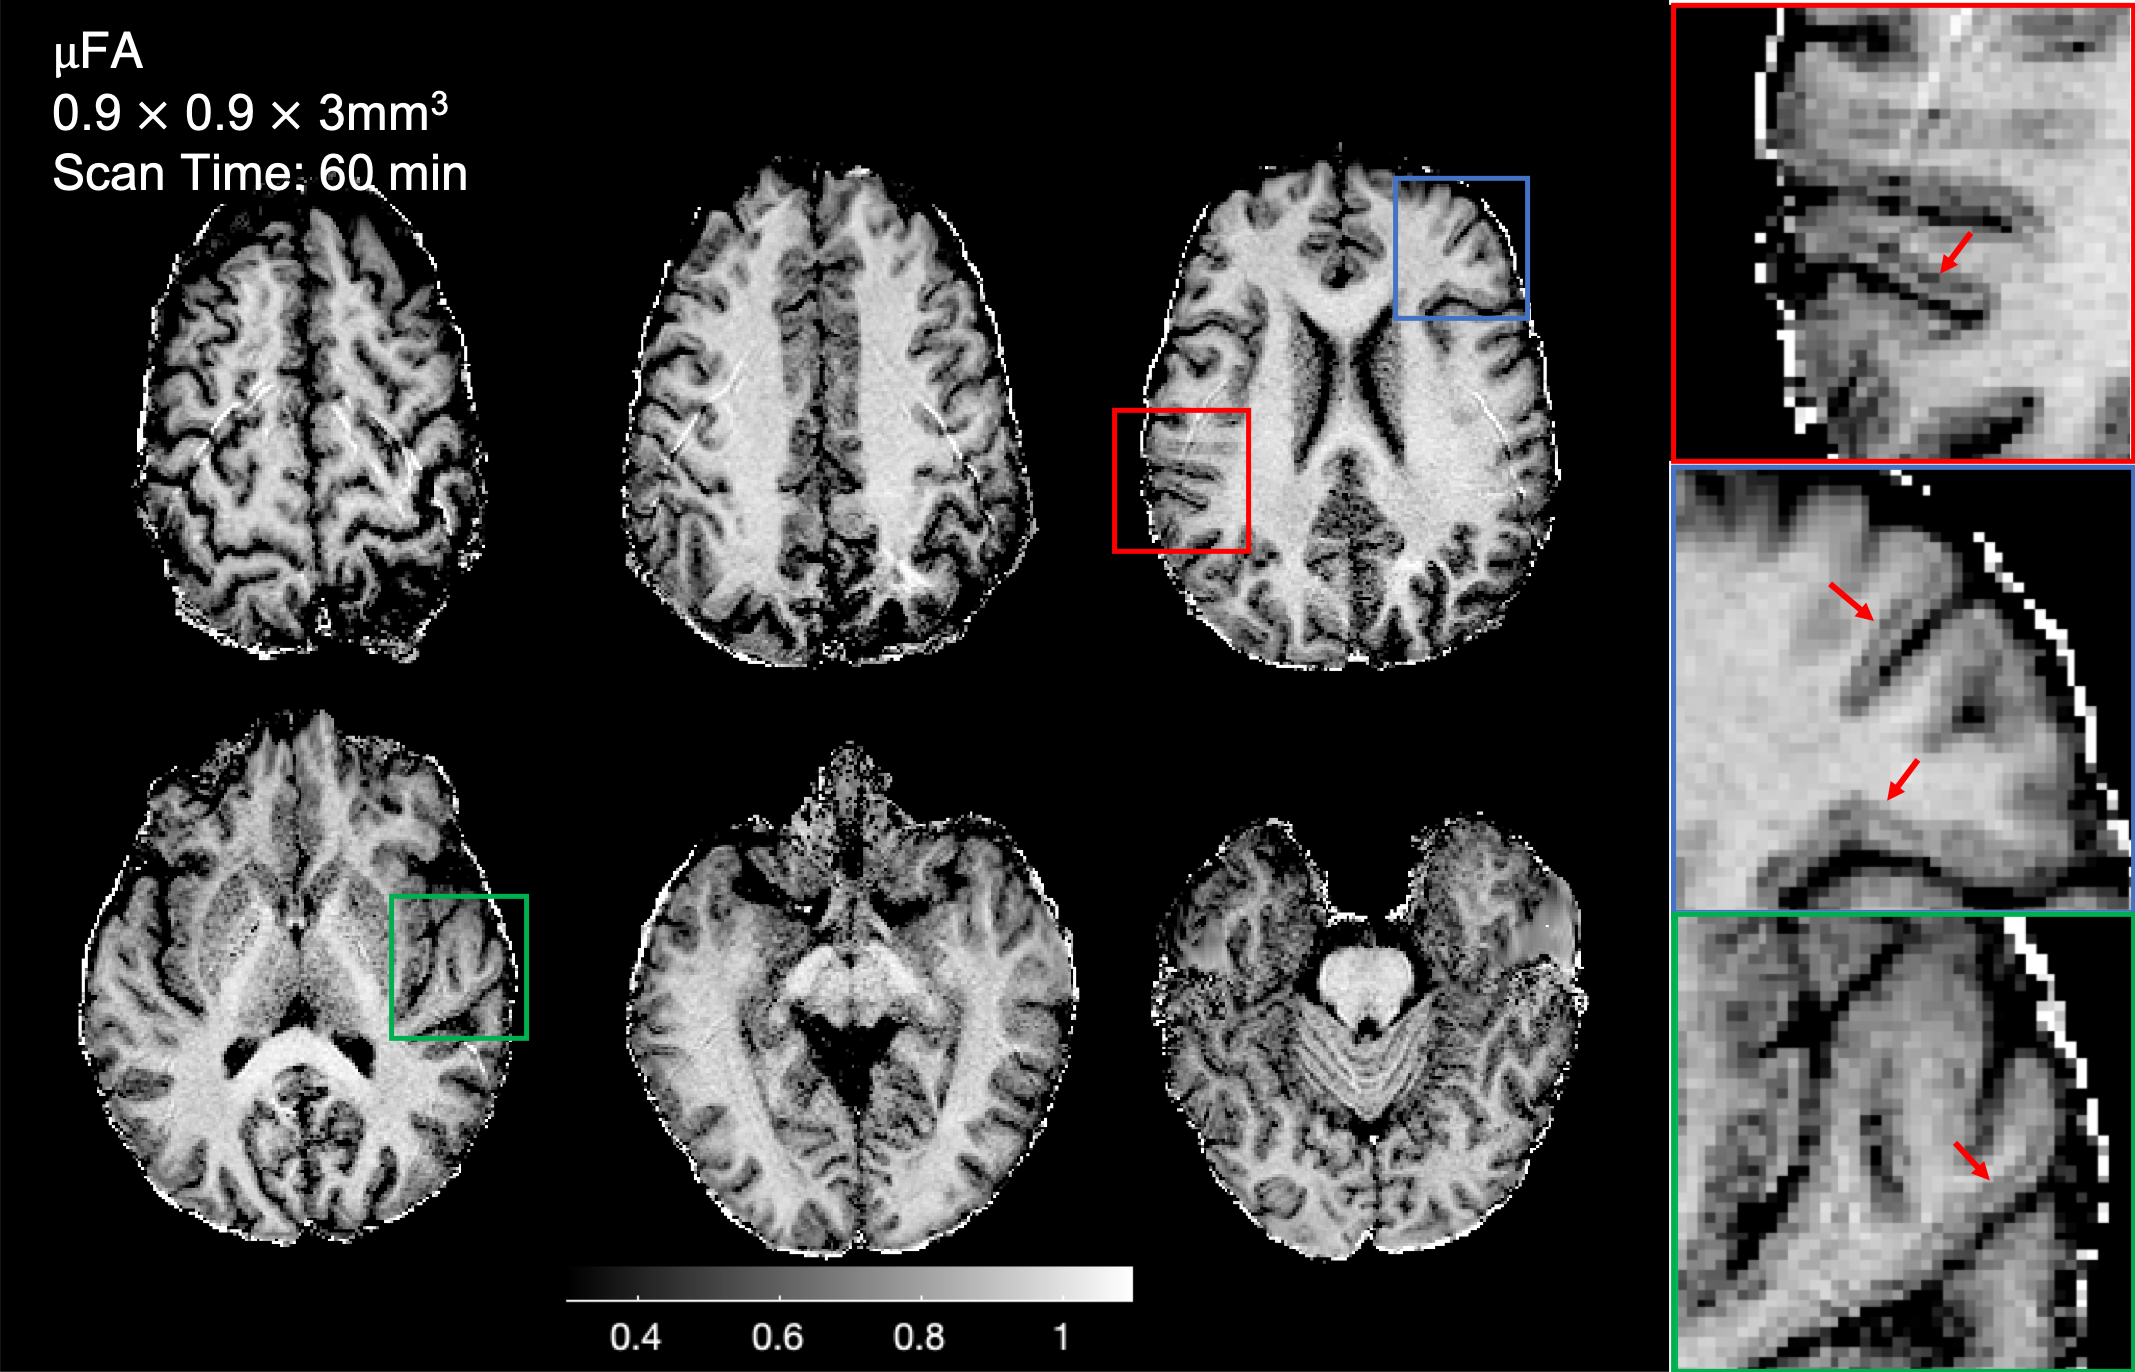

Figure 2: Representative slices from the combined data from the two 30 min MAGNUS-A1 acquisitions with sub-millimeter in-plane resolution. The µFA maps are significantly higher resolution and show fine details in the transition between the white matter and cortex (magnified regions), which are inaccessible at lower resolutions. However, some parallel imaging artifacts are present due to uncorrected first order concomitant fields resulting from the asymmetric gradient coil design.